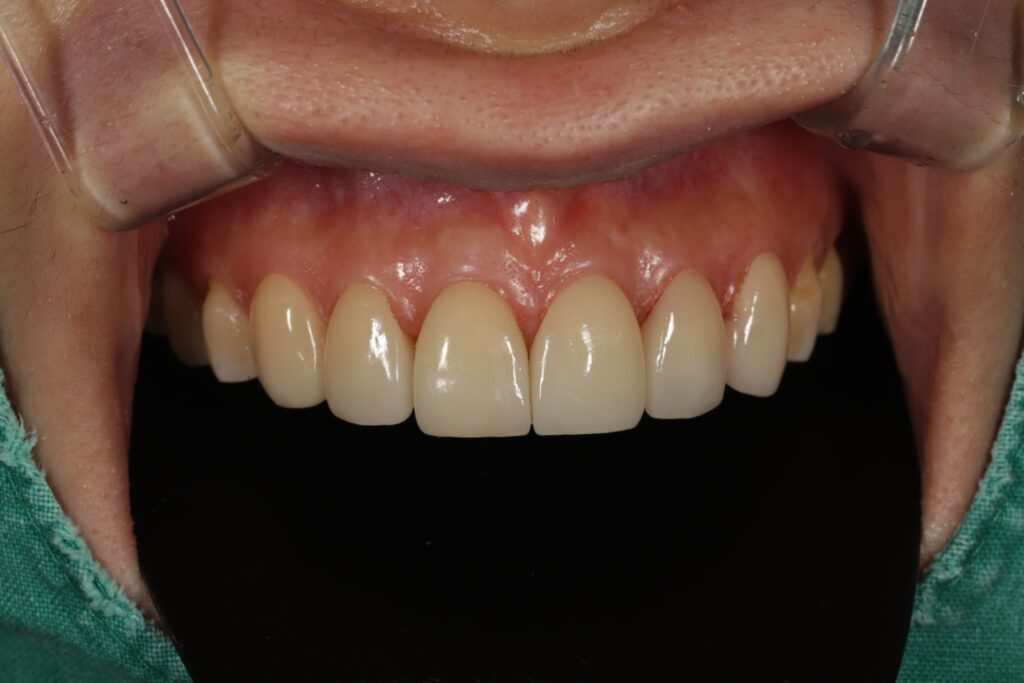

먼저 심미적인 개선이 가장 중요한

위쪽 송곳니부터 송곳니까지

총 6개의 전치부에 대해 e.max empress

라미네이트 베니어를 적용하였습니다.

이를 통해 치아의 색상과 형태를

자연스럽게 개선하고,

전체적인 조화를 맞추는 데 중점을 두었습니다.